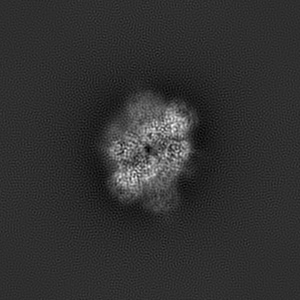

Glycine and glutamate bound GluN1a-GluN2B NMDA receptors in non-active 1 conformation at 2.97 Angstrom resolution

Single-particle

2.97 Å

Sample Organism: Rattus norvegicus

Sample: Hetero-tetrameric GluN1a-GluN2B NMDA receptors

Fitted models: 7saa